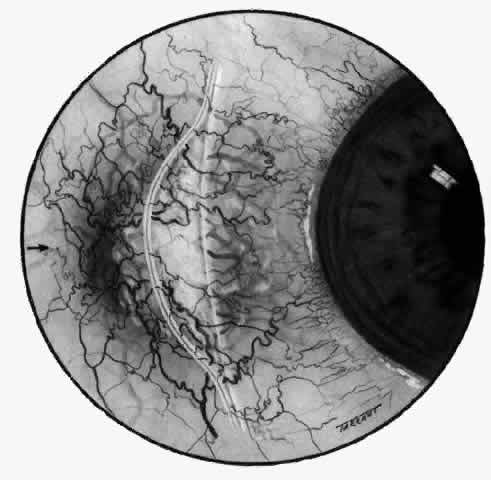

a result of changes in collagen and proteoglycan. The shape of the sclera is determined by the inner layer of the optic cup, the retina, and the choroid. The sclera is derived from a condensation of mesectoderm (from the neural crest). The sclera develops outside the choroid late in development, starting anteriorly. The development of sclera and choroid is in turn induced by the retinal pigment epithelium. Abnormalities of development at this stage may lead to colobomas and in lesser instances to progressive myopia. Development of sclera over the posterior pole is not complete until the end of the fifth month of fetal life.2 From then on, the shape of the sclera is modified by the effect of the intraocular pressure. The elastic fibers in the sclera can be stretched beyond their limit of elasticity when not supported by a fully developed collagenous structure. The whole globe can therefore be distended until 3 years after birth; the lamina cribrosa is the only scleral structure that can be stretched after this age. Although the sclera has a low metabolic activity, it requires some nutrition, which it derives from the underlying choroid and overlying episclera, the sclera being entirely permeable to water, glucose, and proteins. The sclera transmits blood vessels but retains a very scant supply for its own use. However, the sclera is supplied with nerves, particularly in the anterior segment near the muscles; damage to these nerves in destructive scleritis is undoubtedly the major cause of pain in this condition. The nerves also appear to be stimulated by distention of the sclera. The episclera, or Tenon's capsule, provides for part of the nutrition of the sclera and for the cellular response to inflammation. In addition, the episclera also acts as a synovial membrane for smooth movement of the eye and, together with the muscular sheaths to which it is fused, provides a check on excessive movement. The episclera is a fibroelastic structure formed after the development of the sclera from a mesenchymal condensation of the areolar structures of the orbit, possibly in response to eye movement. A deep or visceral layer is closely applied to the sclera. The outer parietal layer combines with the muscle sheaths, fusing first with the visceral layer and then with conjunctiva near the limbus. The subconjunctival space is traversed by only a few fibers, which form very little barrier to edema; it is not a lymphatic space because it contains no endothelium. The parietal layer of Tenon's capsule is penetrated by the muscles, anterior ciliary artery, veins, nerves, and aqueous veins. The two layers of the episclera are thinly joined together by connecting fibers, and each layer is supplied with its own vascular network derived from the anterior ciliary arteries. With the increasing use of anterior segment fluorescein angiography in the early detection of severe necrotizing disease of the sclera, it is necessary to have an understanding of the normal anatomy of the vasculature of the anterior segment of the eye.3–5 The blood supply to this region is enormous, being derived from the anterior ciliary arteries, but with extensive collateral arterial anastomoses to the posterior ciliary arteries at the root of the iris (Fig. 1). The anterior system is readily visible with the slit lamp and by anterior segment fluorescein angiography, especially if the eye is inflamed, and its recognition is of vital importance in the differentiation of episcleral and scleral conditions. The separation and displacement of these vascular layers give the most important clinical clues to the site and, hence, the severity of the inflammation. On slit lamp examination, three layers of vessels are readily visible. The conjunctival plexus, which is the most superficial layer of vessels, can be moved over the underlying structures. The superficial episcleral capillary plexus (Fig. 2) is a radially arranged series of vessels lying within the parietal layer of Tenon's capsule. The vessels in this layer anastomose at the limbus with the conjunctival vessels, with other members of the same plexus, and with the deep plexus. The deep episcleral capillary network (see Fig. 2) is closely applied to the sclera in the visceral layer of Tenon's capsule. The vessels anastomose freely with each other, forming a syncytium. The large vessels to and from the intrascleral plexus traverse the episclera near the insertions of the muscles. The conjunctival and superficial episcleral vessels can be blanched with 1:1000 epinephrine or 10% phenylephrine, but the deep vessels are affected slightly. This is of considerable assistance when attempting to differentiate deep and superficial inflammation.

The direction of flow, the distinction between arteries and veins, and the integrity of the circulation can be determined only by the use of anterior segment fluorescein angiography.4,5 |

ARTERIAL PHASE Anterior Episcleral Arterial Circle The anterior ciliary arteries run radially toward the limbus within Tenon's capsule, giving few, if any, branches until they reach the anterior part of the globe. Their positions are very variable, and they do not always follow the rectus muscles. They bifurcate 2 to 5 mm behind the limbus, and each division runs forward and circumferentially to anastomose with a branch from an adjacent artery. This results in an anterior episcleral arterial circle (Figs. 3 through 5). The divisions of the anterior ciliary arteries are typically superficial at their origins but run deeper at their anastomoses. They occasionally dip too deep to be seen in fluorescein angiograms (Fig. 6).

From the anterior episcleral arterial circle, four distinct circulations are supplied: episcleral, anterior conjunctival, limbal, and iris. Episcleral Circulation Immediately after their origin by bifurcation of the anterior ciliary arteries, the contributions to the anterior episcleral circle divide again to give recurrent branches that run posteriorly and subdivide to form a netlike episcleral plexus (see Fig. 5; Fig.7). The variability of the positioning of the anterior ciliary arteries inevitably leaves large areas of episclera far from such an arterial supply (see Figs. 4, 6, and 7). These areas receive other posterior branches from the episcleral circle. Where the circle runs deep within the sclera, such branches appear as isolated perforating vessels (see Fig. 6). They fill very shortly after the episcleral circle, and they also divide repeatedly as they run posteriorly.

Anterior Conjunctival Circulation Throughout their superficial course, the arteries of the episcleral circle give off fine loops that run forward into the limbal reflection of the conjunctiva before curving back radially and dividing to form the lacework of the anterior conjunctival capillary plexus (see Fig. 2). The delicate column of blood within the anterior conjunctival loops may be punctuated by a string of individual erythrocytes, suggesting that the lumen is approximately 12 μm in diameter. Anterior conjunctival loops may also arise from perforating posterior branches of the episcleral circle (see Fig. 6). The anterior conjunctival circulation, supplied by the anterior ciliary arteries, always fills before the posterior conjunctival circulation, which is derived from the posterior tarsal vessels (see Figs. 4 and 5). The watershed zone between these sources can fill very late (see Fig. 5). However, anterior conjunctival loops do sometimes anastomose with arteries of similar caliber derived from the posterior tarsal circulation. Limbal Arcades Limbal arcades are supplied by anterior branches from the episcleral circle. Their origins are often shared with those of the anterior conjunctival loops, and, where the circle runs deep, they too are derived from the perforating posterior branches. They often fill very late during a normal angiogram (see Fig. 7). The limbal capillary loops never leak fluorescein, even during high-dose angiograms, suggesting that their endothelial cells are united by tight junctions. Iris Vessels The first flush of fluorescein within the anterior episcleral arterial circle always coincides with filling of the radial arterioles of the iris. It may be implied from this that the iris receives a major supply from the anterior ciliary circulation (see Fig. 6). In some angiograms, the iris circulation appears to derive directly from the episcleral circle. This raises the possibility that the “major circle of the iris” and the episcleral arterial circle are less distinct entities than has hitherto been presumed. VENOUS PHASE Anterior ciliary veins accompany the arteries, but there is no well-organized venous ring corresponding to the anterior episcleral arterial circle. The posterior episcleral branches of the arterial circle are paralleled by centripetal venules, and looping anterior conjunctival venules are interspersed between the arterioles (see Figs. 4 and 5). The posterior conjunctiva drains back into the tarsal circulation. CAPILLARY PHASE The episcleral capillary net is often difficult to discern below the more prominent conjunctival circulation. It is most clearly seen when the conjunctival circulation fills late for anatomic or pathologic reasons. The anterior conjunctival capillary plexus forms an interlacing network between the anterior conjunctival arterioles. Perfusion of the watershed zone that separates the territories supplied by the anterior ciliary and posterior tarsal systems may be delayed by as much as 15 seconds after first flush (see Figs. 5 and 7). However, this region is often crossed by arteriolar anastomoses between the two circulations, and the destination of venous blood is irrespective of its origin from the anterior ciliary or posterior tarsal circulations. |